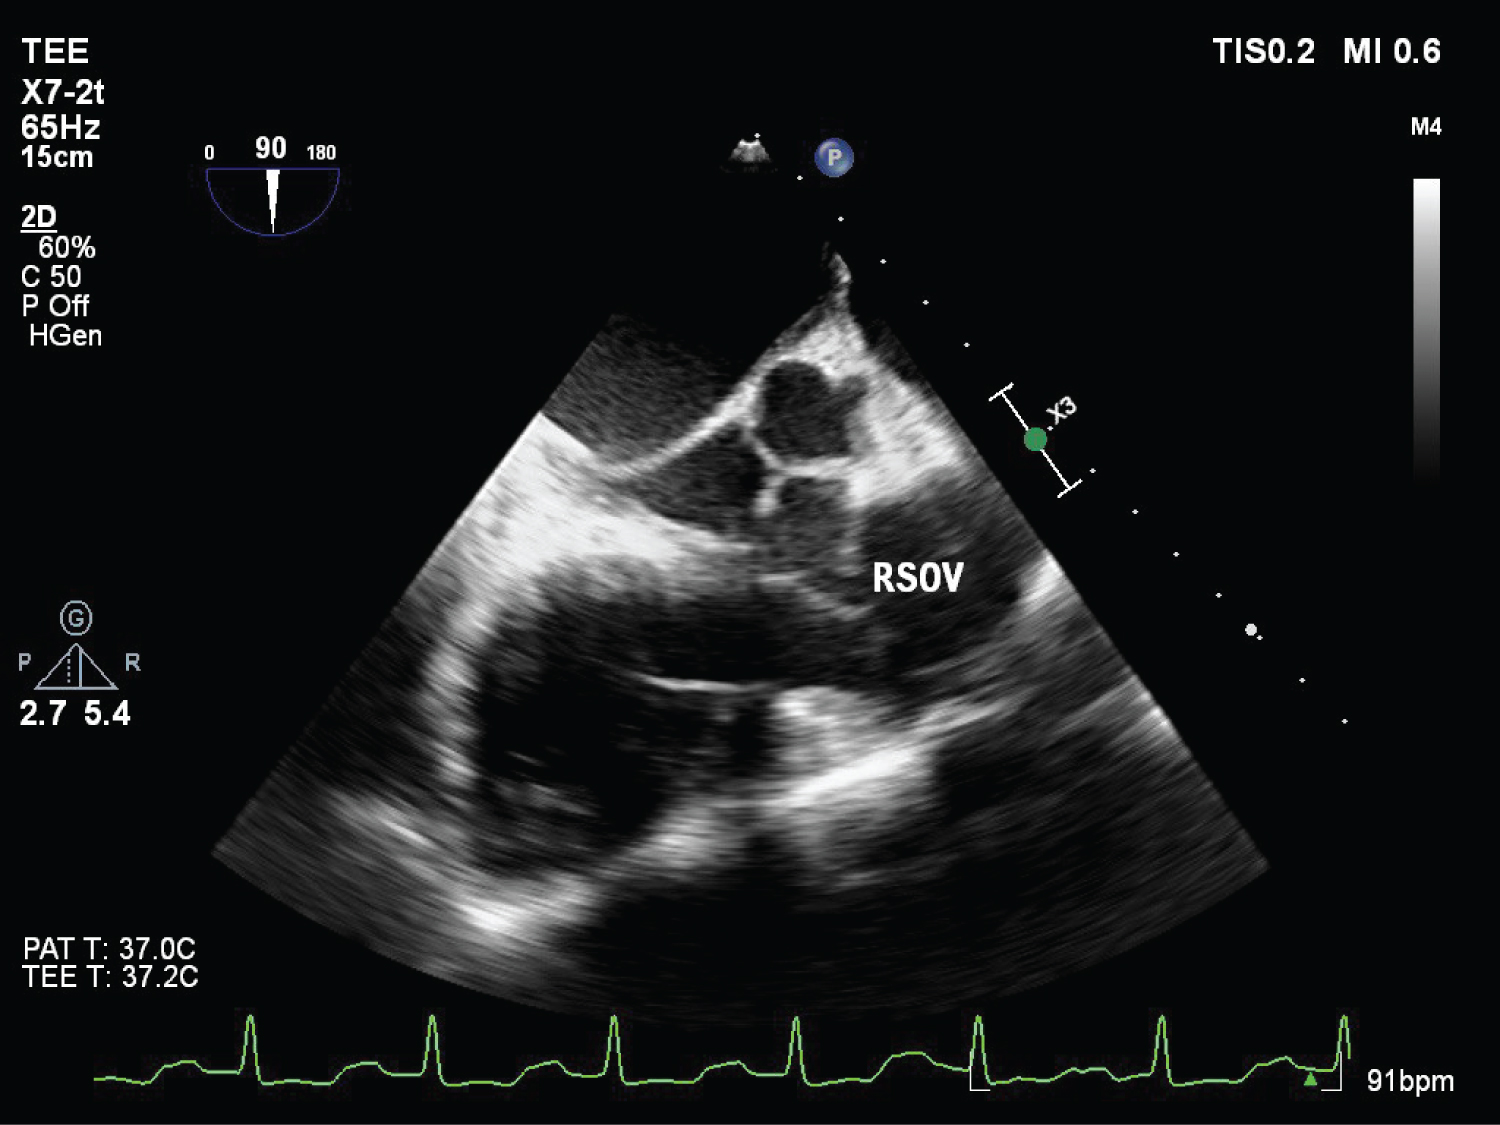

On echocardiography, aneurysmal appearance of the involved sinus and the presence of a “windsock,” protruding into the receiving chamber are characteristic of RSOV [7] (Figure 1, Figure 2, Figure 3, Figure 4 and Figure 5) ( Video 1 and Video 2 ).

Figure 4: (TEE) Mid esophageal RV inflow outflow view post surgical correction of RSOV and VSD repair with RV ridge resection. View Figure 4

Figure 5: (TEE) Mid esophageal long axis view with colour Doppler post-surgical correction showing absence of VSD and respected RV ridge. View Figure 5

Other than the TTE findings an additional Perimembranous VSD was documented on TEE examination which was not reported in TTE.

On TEE evaluation adequate RSOV repair and no residual VSD shunt was confirmed. Patient came off cardiopulmonary bypass uneventfully. Patient’s self-heart rhythm was restored, hence pacing was switched off.